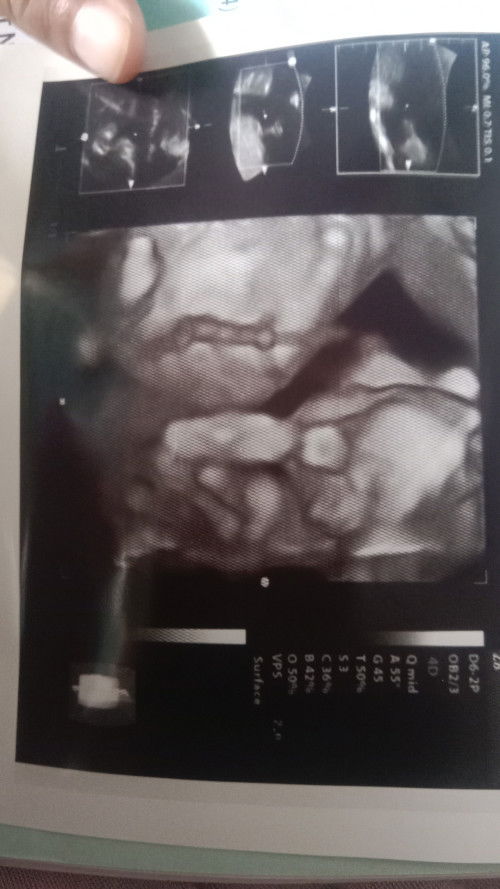

Alhamdulilah bun aku td usg hasilnya bagus semua

Hasil usg 18 mgg 4